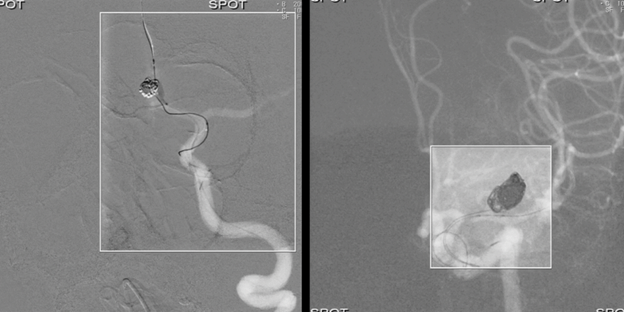

Доступна діагностика - це ангіографічна система Alphenix Core+

Ангіогафічна система Alphenix Core+ від Canon Medical є базовою у своєму роді. Її надійність підкріплюється надзвичайно потужним рівнем візуалізації. Завдяки Alphenix Core+ ви матимете змогу проводити якісні інтервенційні процедури, із можливістю постійно покращувати рівень діагностики. Зумовлено це можливістю розширювати її конфігурації.

Новий рівень візуалізації

Для закладів, що прагнуть досягти більшого за менших витрат, найкращим вибором стане ангіограф Alphenix Core+. Ця система повністю відповідає сучасним вимогам до проведення інтервенційних процедур із можливістю розширення конфігурації в майбутньому.

• Цифрова субтракційна ангіографія (DSA);

• Режим Spot Fluoro передбачає асиметричну, сфокусовану на проблемній ділянці колімацію з одночасним відображенням оточуючої області та збереженням дози до 70%.